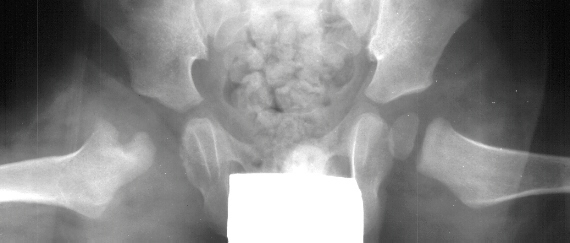

- Post Operative Day 18: R hip Xray: subluxation of R hip, possible metaphyseal

lucency consistent with osteomyelitis. Taken to OR for repeat I & D

of R hip via posterior approach with Penrose drains and hip spica cast

(15cc seropurulent fluid drained). Antibiotics changed to Oxacillin 225mg

IV q4.

- 2 month Office Follow Up: Rt hip Xray: progressive destruction of capital

femoral epiphysis, cystic changes in metaphysis consistent with AVN.